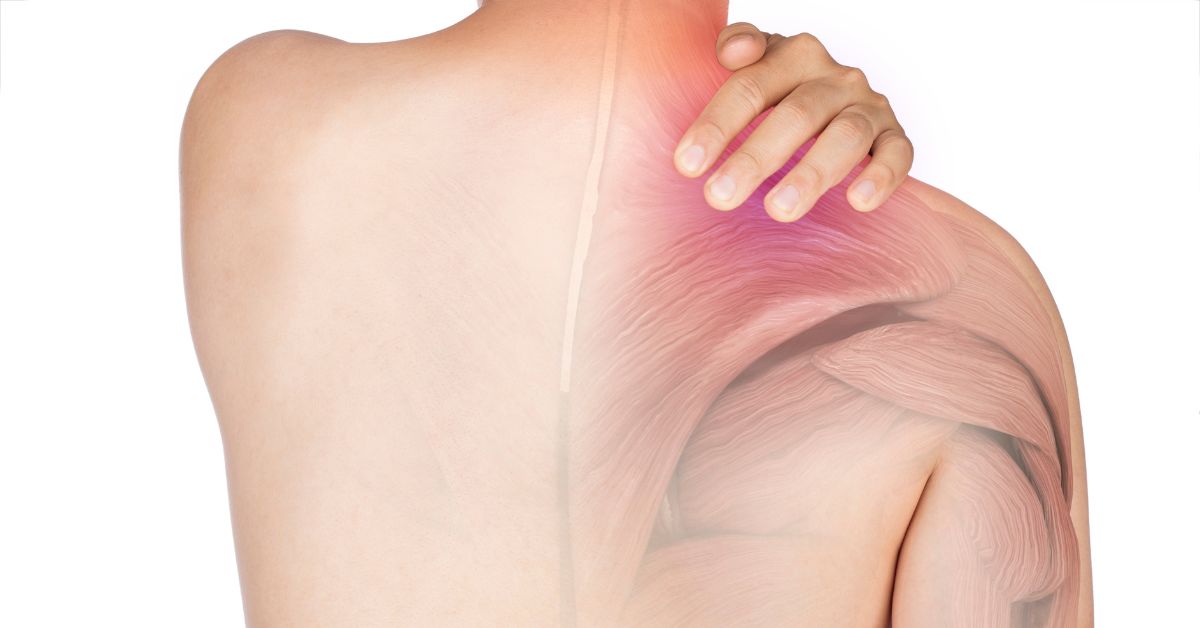

Symptoms to Watch For

Early symptoms of Dropped Head Syndrome can be subtle, but recognizing them early may improve treatment outcomes. Common signs include: Gradual forward tilting of the head, Neck fatigue after short periods of activity, Limited ability to lift or rotate the head, Pain or tension in the upper back, shoulders, and neck, Tingling or numbness in the arms (known medically as paresthesia). In young adults, these symptoms may be mistakenly attributed to screen time, improper ergonomics, or general fatigue. However, if symptoms persist or worsen, a medical evaluation is recommended.